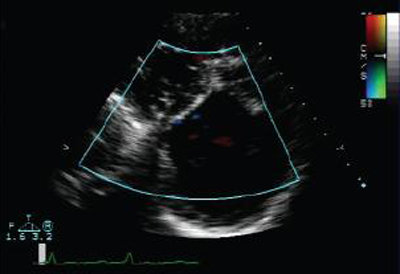

Ecocardiografia com Doppler em um paciente com regurgitação pulmonar após reparo de tetralogia de Fallot, revelando via de saída do ventrículo direito não obstruída. O paciente tem ventrículo direito não restritivo

De: Chaturvedi RR, Redington AN. Heart. 2007 Jul;93(7):880-9; usado com permissão